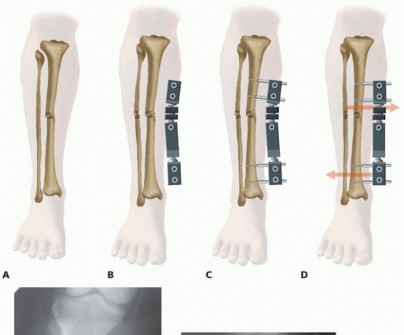

Monotube Four-Pin Frame Application for Tibial Shaft Fracture Use of the large monotube fixators facilitates rapid placement of these devices, with the fixed-pin couple acting as pin templates ( TECH FIG 4). Two pins are placed through the fixator pin couple proximal to the fracture. They are inserted parallel to each other at fixed distances set by the pin clamp itself. These are usually oriented along the direct medial or anteromedial face of the tibial shaft. Once the pins are inserted, the pin clamp is tightened to secure them in place. 540

### TECH FIG 4 • A. Tibial shaft fracture with displacement. B. Monotube fixator adjusted to length and orientation, with all ball joints and the telescoping central body loosened. C. Proximal two pins applied using pin couple as template. D. Distal pins inserted and fracture reduced with all ball joints locked to maintain reduction. Telescoping body is also locked to maintain axial alignment. E,F. Injury and reduction radiographs using a large-body monotube fixator for an open comminuted tibial shaft fracture. The monotube body is then attached to the proximal pin couple and longitudinal traction applied to achieve a “gross” reduction. The fixator body and distal multipin clamp are oriented along the shaft of the tibia. The proximal and distal ball joints should be freely movable with the telescoping body extended. Two pins are placed through the pin couple distal to the fracture and tightened. Care must be taken to allow adequate length of the monotube frame before final reduction and tightening of the body. 11 541 Using the proximal and distal pin clamps as reduction aids, the fracture is manually reduced. The proximal and distal ball joints are then tightened, accomplishing a reduction. At this point, the telescoping body can be extended or compressed to dial in the axial alignment. When length is achieved, the body component is tightened to maintain axial length. Monotube bodies have a very large diameter, which limits the amount of shearing, torsional, and bending movements of the fixation construct. Axial compression is achieved by releasing the telescoping mechanism. Dynamic weight bearing is initiated at an early stage once the fracture is deemed stable. In fractures that are highly comminuted, weight bearing is delayed until visible callus is achieved and sufficient stability has been maintained. The telescopic body allows dynamic movement in an axial direction, which is a stimulus for early periosteal healing.